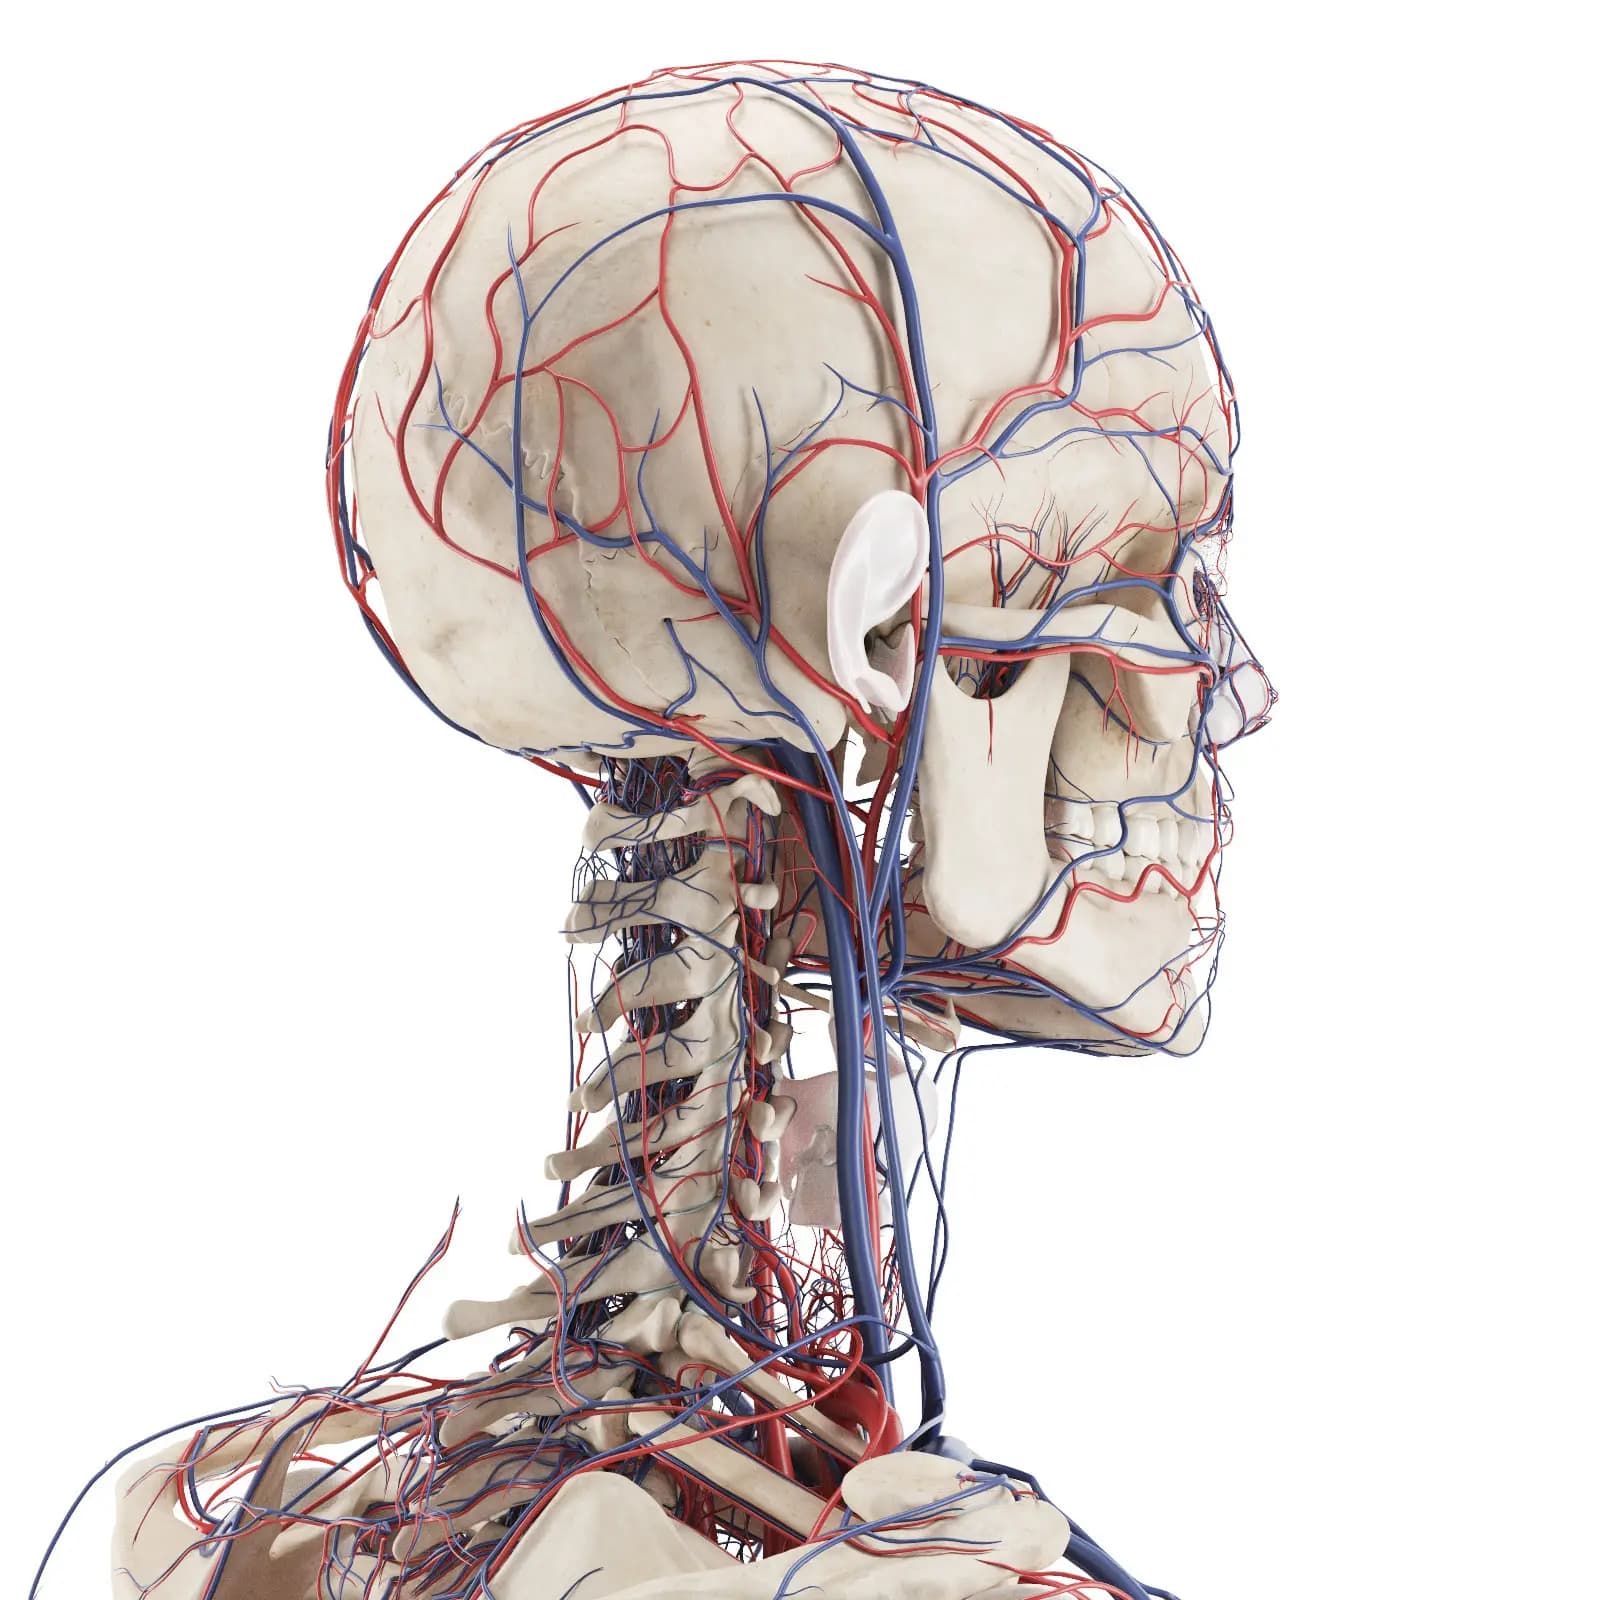

3d Rendered Medical Illustration Of The Vascular System Of The Head